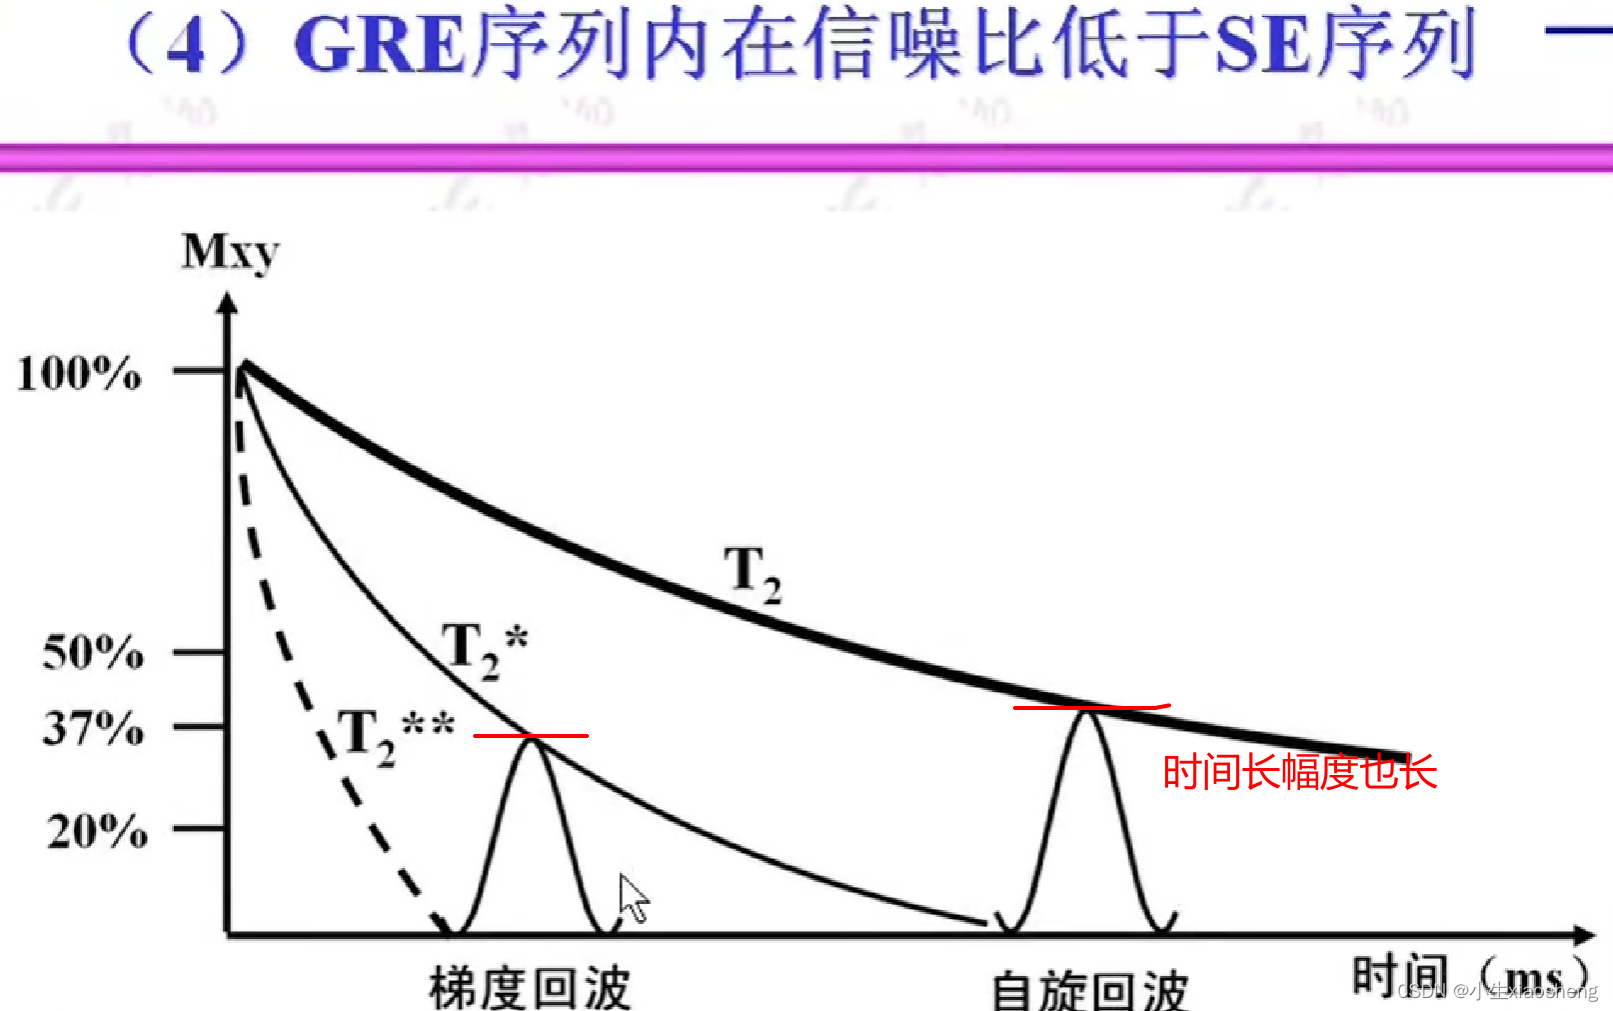

五、梯度回波类序列

GRE就是梯度回波